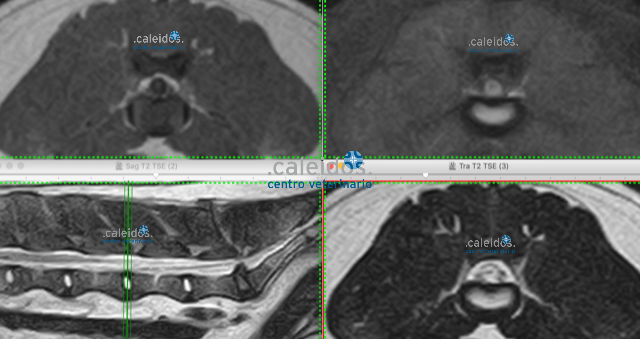

Getting to the bottom of the root of your pet's illness is our goal at Caleidos clinic, so it's essential to use every tool that can allow us to achieve it. Among these are MRI. This investigation, due to its scarce availability in the area and in particular in the veterinary field, although particularly suitable for the study of soft tissue and minimally invasive (it requires only mild sedation and does not emit harmful radiation for the animal), was, for years, performed only after resorting to other more widespread and easier techniques. Today, MRI is known as the diagnostic method of choice for brain, medullary, ligament, cartilage and some cardiovascular diseases, ones that can be promptly identified in our facility thanks to a cutting-edge, highly performing MRI equipment and to specialist staff.

In line with its principle of continuous renewal and updating, in 2019 Caleidos veterinary clinic added new equipment for MRI. It is a human total-body machine, which allows for faster production of images in higher resolution, of relatively larger anatomical areas. Currently in the clinic we have two MRI machines, so we can examine several patients simultaneously, reducing the time of the test and therefore of sedation of the animal and speeding up information times.